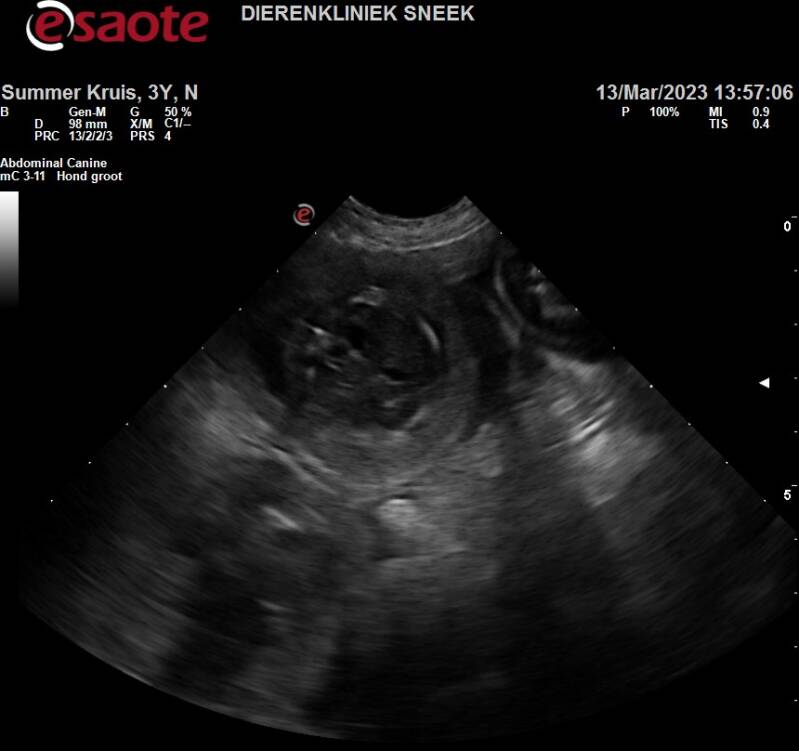

Vandaag zijn we voor een dracht echoscopie geweest...

Met onze Summer voor een drachtechoscopie geweest en wel op 6 weken dracht.

Het was iets later in de dracht daar de dekking goed was gelukt, maar erg laat was in de loopsheid.

Maar we kunnen vermelden dat ze in blijde verwachting is.

Het aantal blijft nog even een verrassing.

De Dracht-echoscopie